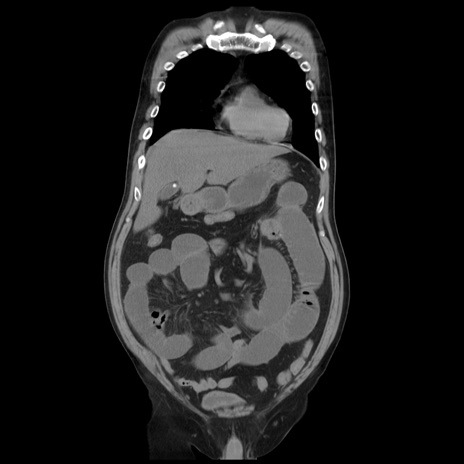

矢状断像